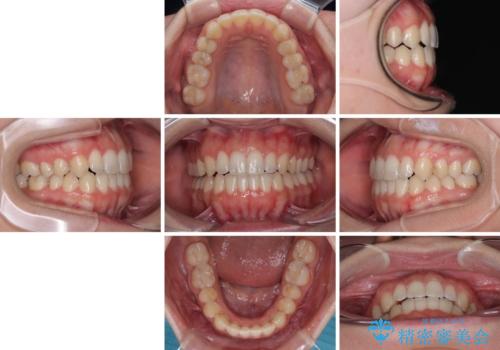

【モニター】オープンバイトをインビザライン矯正で治す

- 1年10ヶ月

- 前歯の開咬を気にして来院された患者様です。

開咬の治療は、前歯を閉じるように動かすとともに、上下臼歯を圧下(骨内にめり込ませる)させることで進めて行きます。

インビザラインは臼歯の圧下を効果的に行えるため、インビザラインを用いて矯正治療を行うこととしました。

オープンバイトは舌の突出癖により誘発され、治療後も突出癖が残っている容易に後戻りしてしまいます。

治療期間を短縮するためにも、舌突出癖の改善が極めて重要となります。